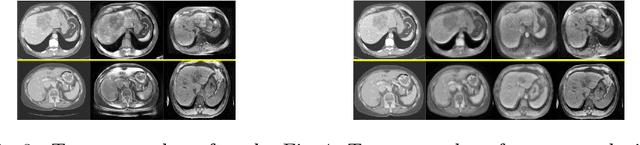

Abstract:Deep neural networks have shown exceptional learning capability and generalizability in the source domain when massive labeled data is provided. However, the well-trained models often fail in the target domain due to the domain shift. Unsupervised domain adaptation aims to improve network performance when applying robust models trained on medical images from source domains to a new target domain. In this work, we present an approach based on the Wasserstein distance guided disentangled representation to achieve 3D multi-domain liver segmentation. Concretely, we embed images onto a shared content space capturing shared feature-level information across domains and domain-specific appearance spaces. The existing mutual information-based representation learning approaches often fail to capture complete representations in multi-domain medical imaging tasks. To mitigate these issues, we utilize Wasserstein distance to learn more complete representation, and introduces a content discriminator to further facilitate the representation disentanglement. Experiments demonstrate that our method outperforms the state-of-the-art on the multi-modality liver segmentation task.

Abstract:A deep learning model trained on some labeled data from a certain source domain generally performs poorly on data from different target domains due to domain shifts. Unsupervised domain adaptation methods address this problem by alleviating the domain shift between the labeled source data and the unlabeled target data. In this work, we achieve cross-modality domain adaptation, i.e. between CT and MRI images, via disentangled representations. Compared to learning a one-to-one mapping as the state-of-art CycleGAN, our model recovers a many-to-many mapping between domains to capture the complex cross-domain relations. It preserves semantic feature-level information by finding a shared content space instead of a direct pixelwise style transfer. Domain adaptation is achieved in two steps. First, images from each domain are embedded into two spaces, a shared domain-invariant content space and a domain-specific style space. Next, the representation in the content space is extracted to perform a task. We validated our method on a cross-modality liver segmentation task, to train a liver segmentation model on CT images that also performs well on MRI. Our method achieved Dice Similarity Coefficient (DSC) of 0.81, outperforming a CycleGAN-based method of 0.72. Moreover, our model achieved good generalization to joint-domain learning, in which unpaired data from different modalities are jointly learned to improve the segmentation performance on each individual modality. Lastly, under a multi-modal target domain with significant diversity, our approach exhibited the potential for diverse image generation and remained effective with DSC of 0.74 on multi-phasic MRI while the CycleGAN-based method performed poorly with a DSC of only 0.52.